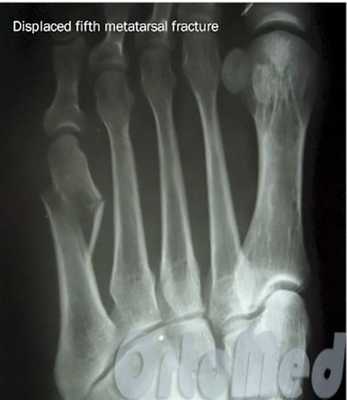

Большинство переломов плюсневых костей является результатом прямого сдавления, например при падении тяжелого предмета на ногу. Непрямой механизм, заключающийся в скручивании переднего отдела стопы, часто приводит к перелому основания V плюсневой кости. Подошвенное сгибание и инверсия напрягают сухожилие короткой малоберцовой мышцы и могут вызвать отрыв шиловидного отростка или бугра у основания V плюсневой кости. Если первоначальным (исходным) механизмом является инверсия, типичен поперечный перелом шиловидного отростка без смещения.

Отрывной перелом класса В у основания V плюсневой кости без смещения требует наложения давящей повязки с нагрузкой на конечность по мере переносимости. Больным с сильными болями может помочь ношение короткого гипсового сапожка в течение 3 нед. Затем показано ношение супинатора для поддержки свода стопы. Следует быть внимательным, чтобы не спутать поперечный перелом проксимального отдела диафиза V плюсневой кости с переломом Джонса, проходящим через ее бугристость. Поперечные переломы, располагающиеся выше бугристости, имеют совсем иной прогноз и лечение. При них наблюдается высокая частота замедленного сращения и несращения.

Аксиома: поперечный перелом основания V плюсневой кости не следует путать с переломом Джонса, проходящим через ее бугристость. Лечение и прогноз для этих переломов различные.

Поперечные переломы проксимального отдела диафиза V плюсневой кости лечат иммобилизацией в коротком гипсовом сапожке. Прогноз в этих случаях сомнителен и вероятность замедленного сращения и несращения высока.

• Перелом Джонса: травматический поперечный перелом проксимальной части диафиза 5-й плюсневой кости

- Перелом Джонса: травматический перелом кости на границе диафиза и метафиза:

Дистальнее межплюсневого сустава

- Перелом Джонса: избыточное отведение стопы, находящейся в положении подошвенного сгибания

• ↑ риск несрастания отломков при проксимальных переломах 5-й плюсневой кости вследствие слабого кровоснабжения этой зоны

• Остеосинтез винтами/пластиной при переломе Джонса: как в остром периоде, так и при замедлении консолидации перелома